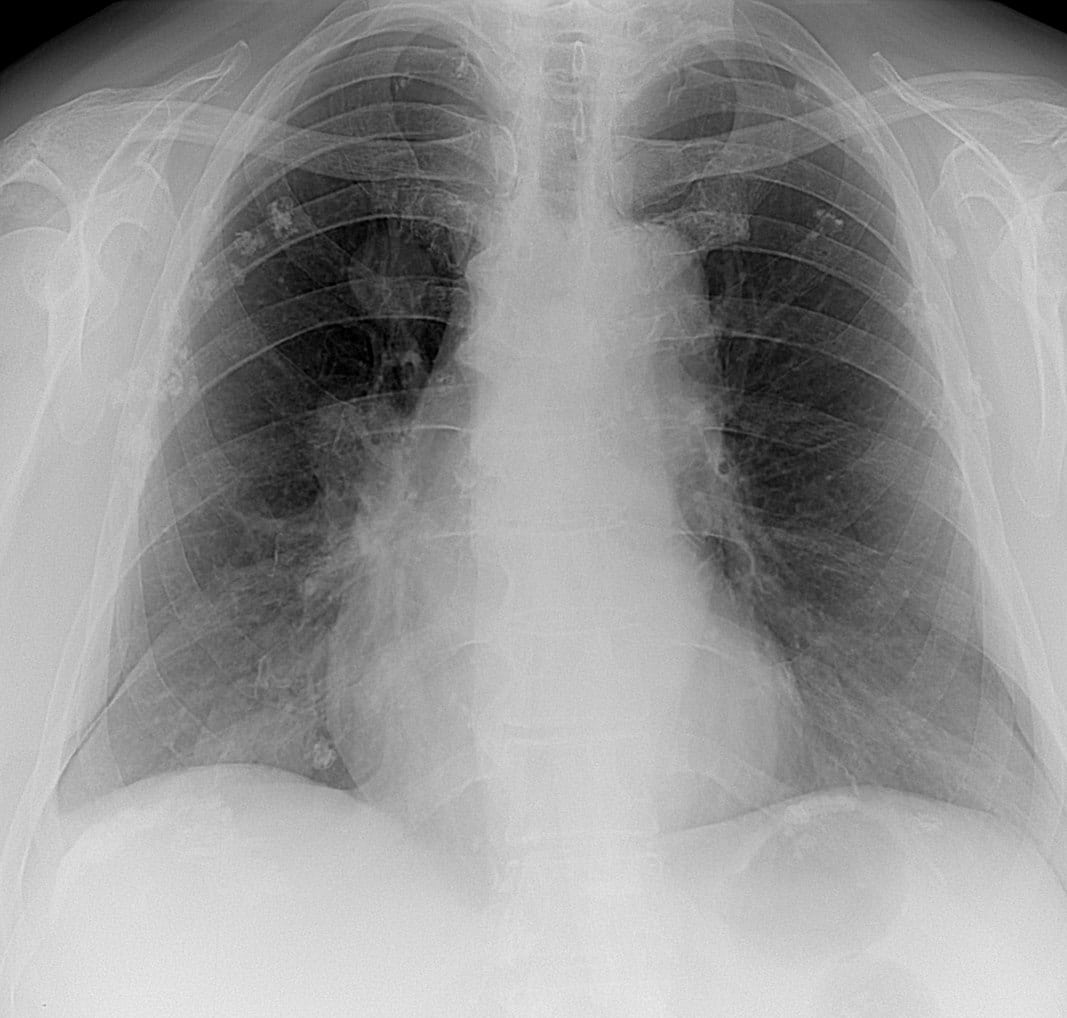

Метастази в легенях